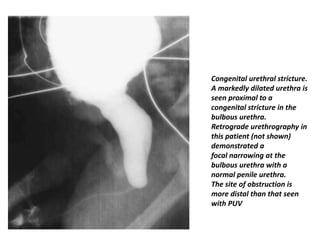

Congenital urethral stricture

• Although most urethral strictures in males are

posttraumatic, there are rare reports of congenital urethral

strictures of the bulbous urethra in neonates and older

children

• It is secondary to a failure of canalization of the cloacal

membrane during fetal development

• Diagnosis is by VCUG or retrograde urethrography. VCUG

will demonstrate focal narrowing of the bulbous urethra,

while retrograde urethrography will confirm a normal

penile urethra. Other causes of urethral stricture, including

trauma, must be excluded.

• The site of urethral narrowing in congenital urethral

stricture is distal to the external urethral sphincter, which

differentiates this entity from PUV

Congenital urethral stricture.

A markedly dilated urethra is

seen proximal to a

congenital stricture in the

bulbous urethra.

Retrograde urethrography in

this patient (not shown)

demonstrated a

focal narrowing at the

bulbous urethra with a

normal penile urethra.

The site of obstruction is

more distal than that seen

with PUV

Congenital urethral stricture •Although most urethral strictures in males are posttraumatic, there are rare reports of congenital urethral strictures of the bulbous urethra in neonates and older children • It is secondary to a failure of canalization of the cloacal membrane during fetal development • Diagnosis is by VCUG or retrograde urethrography. VCUG will demonstrate focal narrowing of the bulbous urethra, while retrograde urethrography will confirm a normal penile urethra. Other causes of urethral stricture, including trauma, must be excluded. • The site of urethral narrowing in congenital urethral stricture is distal to the external urethral sphincter, which differentiates this entity from PUV

• 62.

Congenital urethral stricture. Amarkedly dilated urethra is seen proximal to a congenital stricture in the bulbous urethra. Retrograde urethrography in this patient (not shown) demonstrated a focal narrowing at the bulbous urethra with a normal penile urethra. The site of obstruction is more distal than that seen with PUV